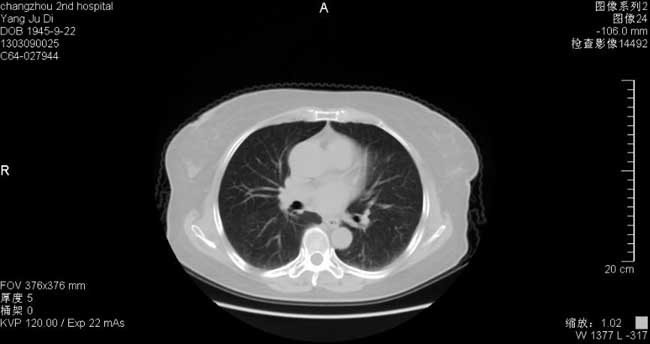

胸部CT(2013-2-19)

ü肺炎给于左氧氟沙星+美洛西林钠舒巴坦抗感染治疗7天后,体温无好转,患者出现胸闷、气急,查血气分析:PH 7.47HCO329.8mmol/lBE5.6mmol/lSO2 89%,提示低氧血症,予吸氧,复查胸部CT提示肺部感染进展.

2013-2-25